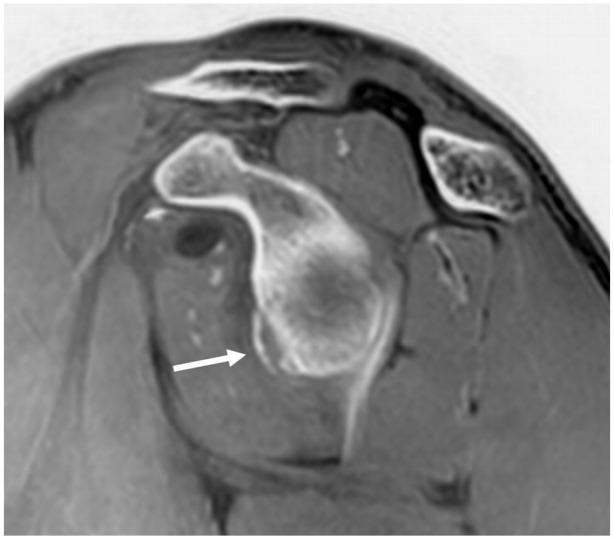

由于技术创新以及对安全和以患者为中心的护理的日益重视,儿童肌肉骨骼成像领域正在取得重大进展。这篇综述探讨了成像方式的最新发展,如先进的磁共振成像、超声创新和人工智能应用。重点包括放射摄影和计算机断层扫描中的辐射剂量降低技术,增强的诊断工具,如对比度增强超声和超高频成像,以及用于病理检测和工作流程优化的人工智能集成。采用先进的方法,如全身磁共振成像和类似计算机断层成像的磁共振成像序列,提高了诊断的准确性,最大限度地减少了辐射暴露,并扩大了非侵入性成像的能力。新兴技术,包括光子计数检测器计算机断层扫描和基于深度学习的重建,正在通过平衡精度和安全性来改变临床实践。人工智能应用正在重塑诊断方法,自动化复杂的评估,并提高效率,尽管外部验证和有限范围等挑战仍然存在。功能成像的进步,如弥散加权成像和正电子发射断层扫描-磁共振成像的整合,正在增强疾病的表征和治疗计划。本综述强调了这些创新的临床影响,强调了标准化方案、跨学科合作和持续研究的必要性,以解决辐射安全和人工智能集成方面未满足的需求。它旨在为医疗保健专业人员提供知识,以利用这些进步改善儿童肌肉骨骼护理的结果。

The field of pediatric musculoskeletal imaging is undergoing significant advancements due to technological innovations and a growing emphasis on safety and patient-centered care. This review explores recent developments in imaging modalities such as advanced magnetic resonance imaging, ultrasound innovations, and artificial intelligence applications. Highlights include radiation dose-reduction techniques in radiography and computed tomography, enhanced diagnostic tools like contrast-enhanced ultrasound and ultra-high-frequency imaging, and the integration of artificial intelligence for pathology detection and workflow optimization. The adoption of advanced methods like whole-body magnetic resonance imaging and computed tomography-like magnetic resonance imaging sequences has improved diagnostic accuracy, minimized radiation exposure, and expanded the capabilities of noninvasive imaging. Emerging technologies, including photon-counting detector computed tomography and deep learning-based reconstructions, are transforming clinical practices by balancing precision and safety. Artificial intelligence applications are reshaping diagnostic approaches, automating complex assessments, and improving efficiency, although challenges such as external validation and limited scope persist. Functional imaging advancements, such as diffusion-weighted imaging and positron emission tomography-magnetic resonance imaging integration, are enhancing disease characterization and treatment planning. This review underscores the clinical impact of these innovations, emphasizing the need for standardized protocols, interdisciplinary collaboration, and continued research to address unmet needs in radiation safety and artificial intelligence integration. It aims to equip healthcare professionals with the knowledge to leverage these advancements for improved outcomes in pediatric musculoskeletal care.